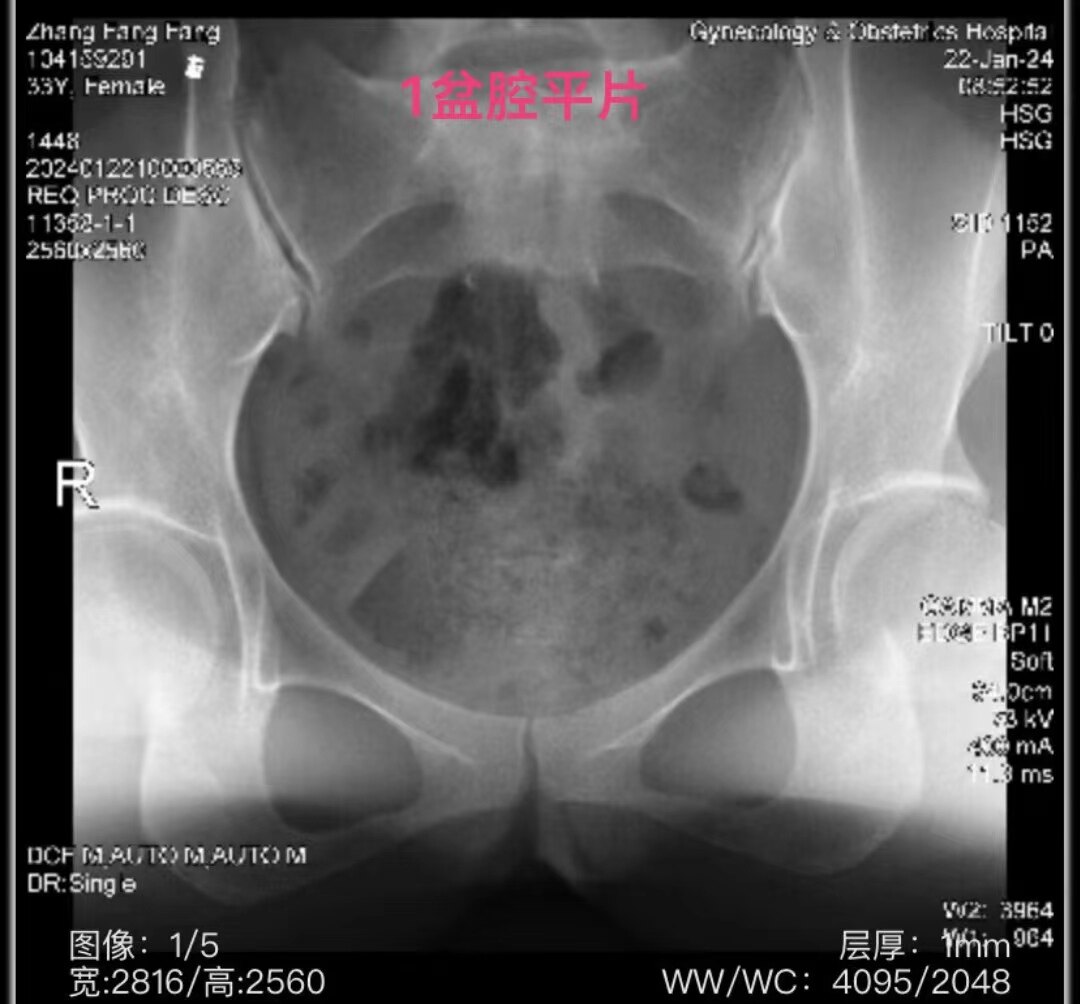

3.jpg

左侧输卵管显影至壶腹部远端,右侧输卵管显影至壶腹部近段。造影剂返回到阴道